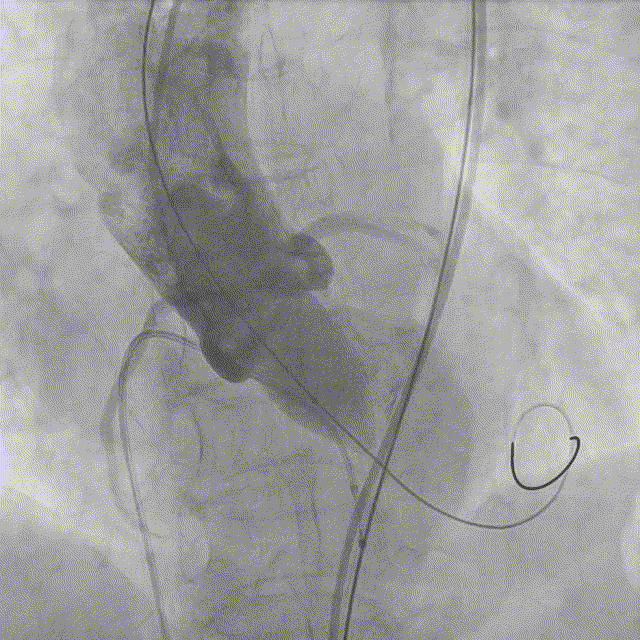

10. 最终造影瓣膜位置理想,无反流,微量周漏。

最终造影

10. 最终造影瓣膜位置理想,无反流,微量瓣周漏。